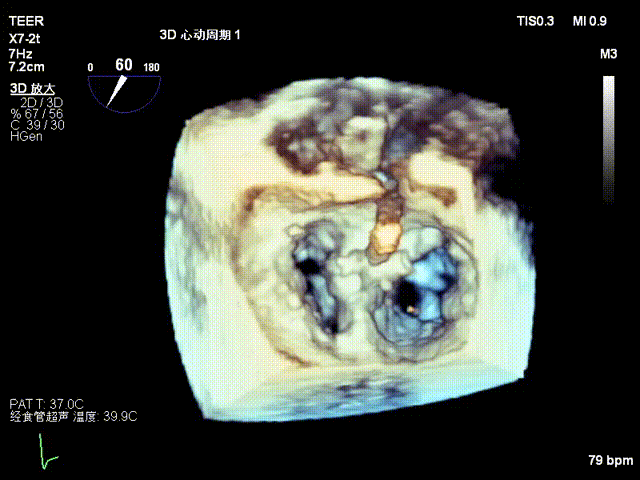

术前影像

左房极小

房间隔增厚

X-plane2区

X-plane2区彩色

3D

3D彩色